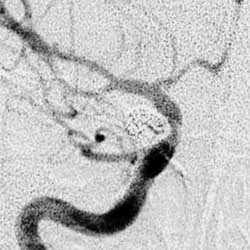

3.腦血管造影是確診顱內動脈瘤必須的檢查方法,對判明動脈瘤的準確位置、形態、內徑、數目、血管痙攣和確定手術方案都十分重要。DSA更為清晰。,經股動脈插管全腦血管造影,可避免遺漏多發動脈瘤。病情在三級以下,腦血管造影應及早進行,三級和三級以上病人可待病情穩定後,再行造影檢查。及早造影明確診斷,儘快手術夾閉動脈瘤,可以防止動脈瘤再次破裂出血。首次造影陰性,可能因腦血管痙攣而動脈瘤未顯影,高度懷疑動脈瘤者,應在3個月後重複造影。